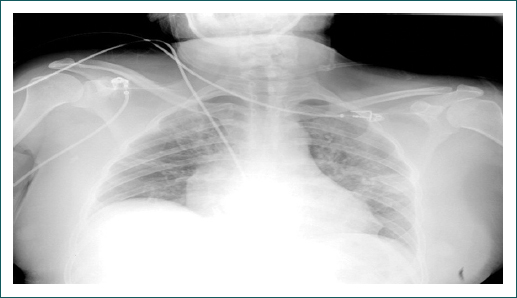

La paciente presentó disminución de la saturación de manera progresiva, llegando a una SpO2 de 84%; la frecuencia respiratoria se mantuvo entre 20-28 rpm (Fig. 2). En este contexto, por hipoxemia persistente, se realizó maniobra de pronación en paciente no intubada con mejoría a los 10 minutos y elevación de la saturación de oxígeno por pulsioximetría hasta 94% (Fig. 3). Esta posición se mantuvo cuatro horas por tolerancia de la paciente. Al encontrar mejoría, se indicó repetir posición prono dos veces al día de cuatro a ocho horas (según tolerancia de la paciente), por cuatro días en total. La paciente presentó mejoría clínica, por pulsioximetría y en la relación PaO2/FiO2, que en supino alcanzó 285 al tercer día posterior a la pronación (Cuadro I). Se realizó nueva PaO2/FiO2, posterior al cuarto día de posición prono con un resultado de 332, y nueva radiografía de tórax tres días después de la maniobra de posición prono, la cual mostró disminución de los infiltrados intersticiales bilaterales (Fig. 4). Se retiró el oxígeno suplementario con SpO2 de hasta 94% al aire ambiente, sin requerimiento de oxígeno suplementario y con una SpO2/FiO2 de 447. Se realizó prueba de caminata de seis minutos con disminución de la SpO2 de 94% a 92%. Se indicó su egreso a los ocho días de hospitalización con signos vitales estables.